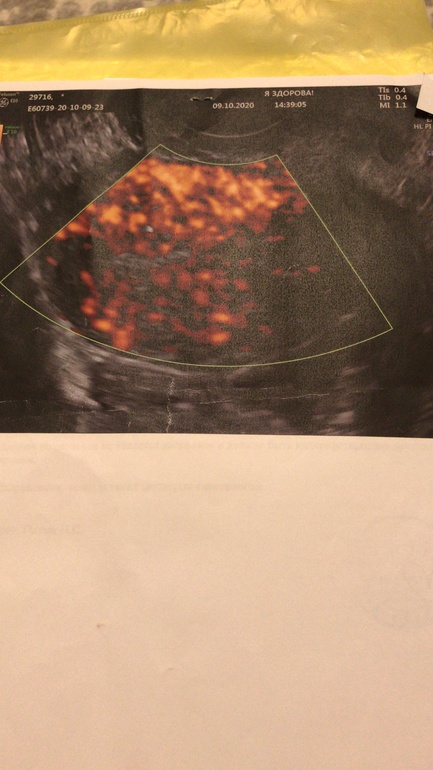

Я сначала ходила на Пиявки с 5-6дц, на след цикл на физио с 6дц. Совмещать нельзя. Вот вам мой результат кровотока до и после) Думаю разница огромная. И я верю в Пиявки , они действительно помогли, кто бы что не говорил.